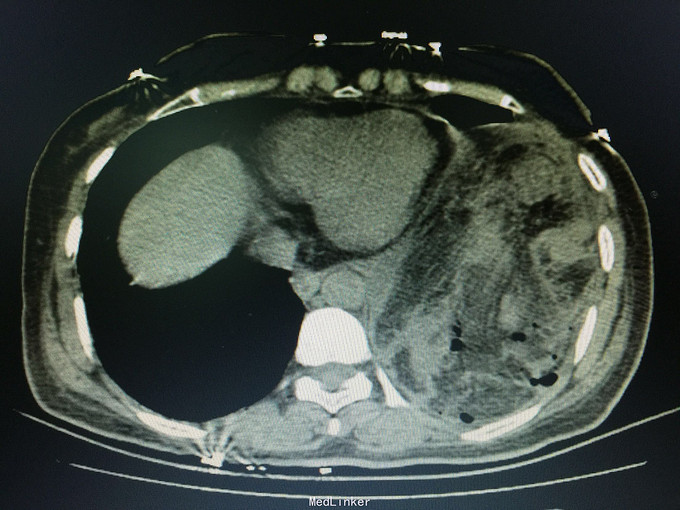

女,41岁, 主诉:腹部胀痛伴不排便、不排气1周, 现病史:一周前无诱因开始腹部胀痛,逐渐加重,以左上腹明显,不排便,不排气,恶心,呕吐数次胃内容物,在当地医院抗炎治疗不见好转,今排腹部平片诊断为“肠梗阻”,来诊。

一般状态可,腹部平坦,未见肠型及蠕动波,脐周压痛,左上腹明显,无腹肌紧张,未及包块,移动性浊音阳性,肠音2次/分。 辅助检查:全腹CT:腹部肠管明显扩张,积液,左侧膈肌局部缺损,腹腔内肠管及系膜组织疝入胸腔。

诊断:膈肌疝,疝内容嵌顿,肠梗阻 处理:手术治疗。

讨论:年轻患者膈肌疝不常见,尤其疝入肠管引起肠梗阻病例更少见;追问病史,该患3年前被刀刺伤左侧季肋部,在外院住院观察,因未见脏器损伤1周后出院,现在考虑为膈肌损伤。